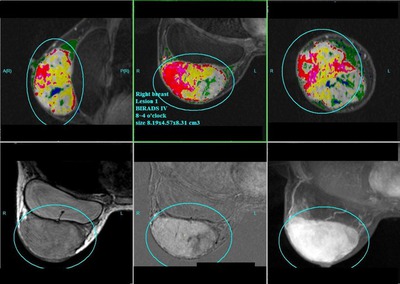

圖一:右乳葉狀瘤分布相當廣泛,且有血管增生之惡性腫瘤跡象

圖二:圖中標示出的部分為矽膠袋

圖三:左下格的血流分析圖顯示出了此腫瘤的惡性特徵

該名婦女於15年前動過矽膠袋隆乳手術,2年前摸到右乳有一小腫塊,由於不痛不癢,加上曾隆乳,不太確定自己摸到的究竟是腫塊或僅是由於隆乳造成,所以一直拖延,僅做了一些中醫療法。近來由於腫塊迅速增大,且乳房腫脹疼痛,懷疑是矽膠袋破裂滲漏,故至整形外科醫師處諮詢。整外醫師為她做了超音波檢查無法確診,遂將其轉診至我的門診,我建議她立即進行乳房專用型磁振造影檢查,結果發現有一8.19*4.57*8.31cm3大小的腫瘤,根據乳房專用型磁振造影的3-D影像,我認為這很可能是葉狀瘤,再加上其血流動態分析,高度懷疑為惡性!經病理切片證實果然為罕見的惡性葉狀瘤!因腫瘤較大,經評估後取出了植入物並進行乳房切除。